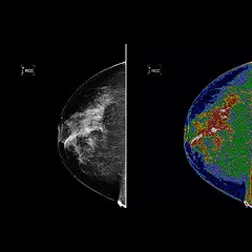

Watch this video by Dr. Deborah Rhodes, M.D. from her December 2010 talk at TEDWomen on why mammograms are not enough for early detection of breast cancer in women with dense breasts. Are you one of the many women who are not getting the right breast screening to prevent breast cancer?